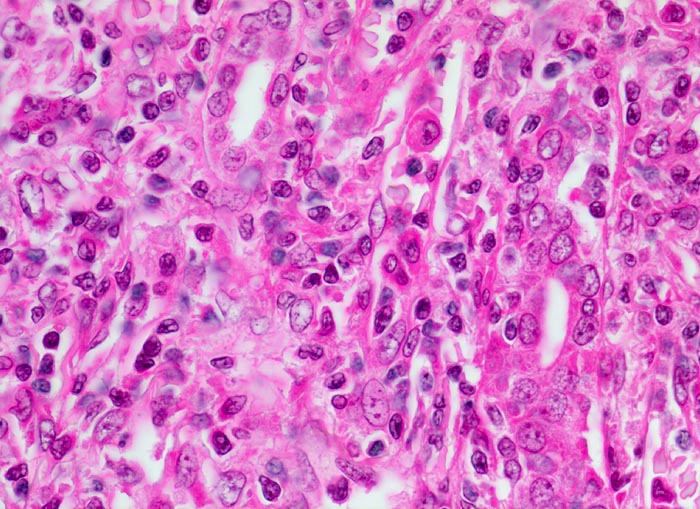

akute Transplantatverwerfung: Tubulitis

Die Grenzen zwischen Tubuli und entzündlich infiltriertem Interstitium sind unscharf. Der Tubulus rechts im Bild wird von zahlreichen mononukleären Entzündungszellen infiltriert.

Das Bild entspricht einer behandlungsbedürftigen aggressiven zellulären akuten interstitiellen Abstossung.